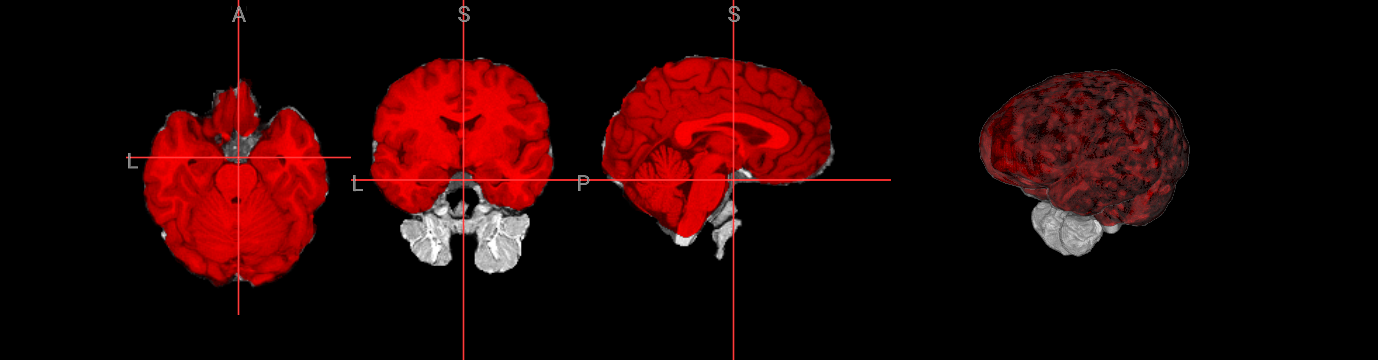

Cerebellum Underestimation: Using the gradient threshold option (-g)#

Problem: Lower brain regions (cerebellum) get cut off

! bet ./fsl_course_data/intro/sub3m0.nii.gz ./output/sub3m0_brain

Image(url='https://raw.githubusercontent.com/NeuroDesk/example-notebooks/refs/heads/main/books/images/fsl_course_bet_sub3m0.png')

Solution: Use gradient threshold (-g) to vary the intensity threshold linearly by slice (getting smaller at the bottom and bigger at the top, or vice versa)

Example: Try -f 0.3 -g 0.2 for balanced results

! bet ./fsl_course_data/intro/sub3m0.nii.gz ./output/sub3m0_f03g02 -f 0.3 -g 0.2

nv.load_volumes([{"path": "./output/sub3m0_f03g02.nii.gz", "colormap": "gray"},

{"path": "./output/sub3m0_brain.nii.gz", "colormap": "green"}])

Image(url='https://raw.githubusercontent.com/NeuroDesk/example-notebooks/refs/heads/main/books/images/fsl_course_bet_sub3m0_g.png')